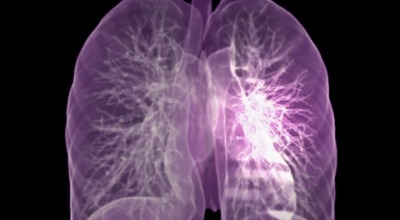

폐암이란?

폐에 발생한 악성 종양을 말하며, 오랜 기간 흡연해온 남성에게서 발병률이 높습니다. 하지만 최근에는 다양한 환경적 요인과 간접흡연의 영향으로 흡연하지 않는 여성에게서도 많이 발생하고 있답니다. 증상을 느껴 병원을 찾았을 때는 이미 수술하기엔 늦은 경우가 많아 사망률이 매우 높은 암입니다. 폐 자체에서 생기거나 다른 장기에서 발생한 암이 폐로 전이되어 나타나기도 하며, 특별한 초기 증상이 없는 경우가 많습니다. 암이 진행된 후에도 일반적인 감기 증상인 기침과 가래 외에 뚜렷한 증상이 나타나지 않아, 증상만으로는 진단이 쉽지 않습니다.